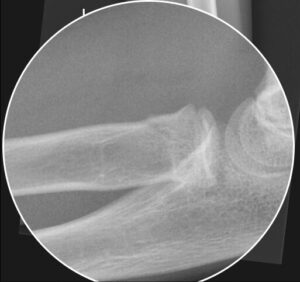

Bildgebung und typische Zeichen

- Standardprojektionen: a.-p. und lateral

- Ergusszeichen: Positives vorderes Fat-Pad („Sail-Sign“), posterior pathognomonisch

- Radiokapitelläre Linie: Muss das Capitellum in allen Ebenen schneiden

- Epiphysenfuge: Frakturlinie, Stufen, metaphysäre Keile